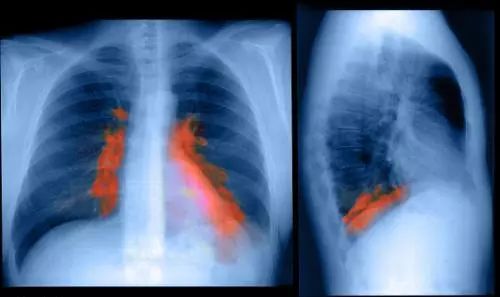

治愈百岁老人的髋部骨折——困难与挑战

随着生活健康水平的提高,我国90岁以上的老人越来越多,百岁老人也渐渐多见。让高龄老人摔倒出现的髋部骨折得到及时救治,健康痊愈,是骨科医生技术能力与医院综合实力的重要体现。我院创伤骨科每年成功救治高龄老年髋部骨折近200例,其中百岁老人占了2-5%。

最大的挑战并非骨折本身,而是老人的基础疾病和并发症。与病人和家属担心的一样,骨科医师面对的高龄病人一般身体条件相对较差,往往患有心脑血管疾病、糖尿病,呼吸系统病、泌尿系统疾病等等基础疾病。同时高龄老人身体储备低,应对骨折并发症的条件能力低,因此老年髋部骨折也被称为“人生的最后一次骨折。”

高龄老人髋部骨折传统的治疗方法是患肢制动或牵引,目前仅适用于内科疾病重、不能耐受麻醉和手术的患者及意识不清和不能自主活动的患者;存在治疗时间长、全身并发症多和病死率高等缺点。目前,为了让老人尽早恢复活动和自理能力,及时有效率的手术治疗已成为治疗老年髋部骨折的主要方法。

要减少老人手术带来的痛苦与风险,我们坚持采用先进的无痛和微创技术。手术损伤小,术后恢复快!